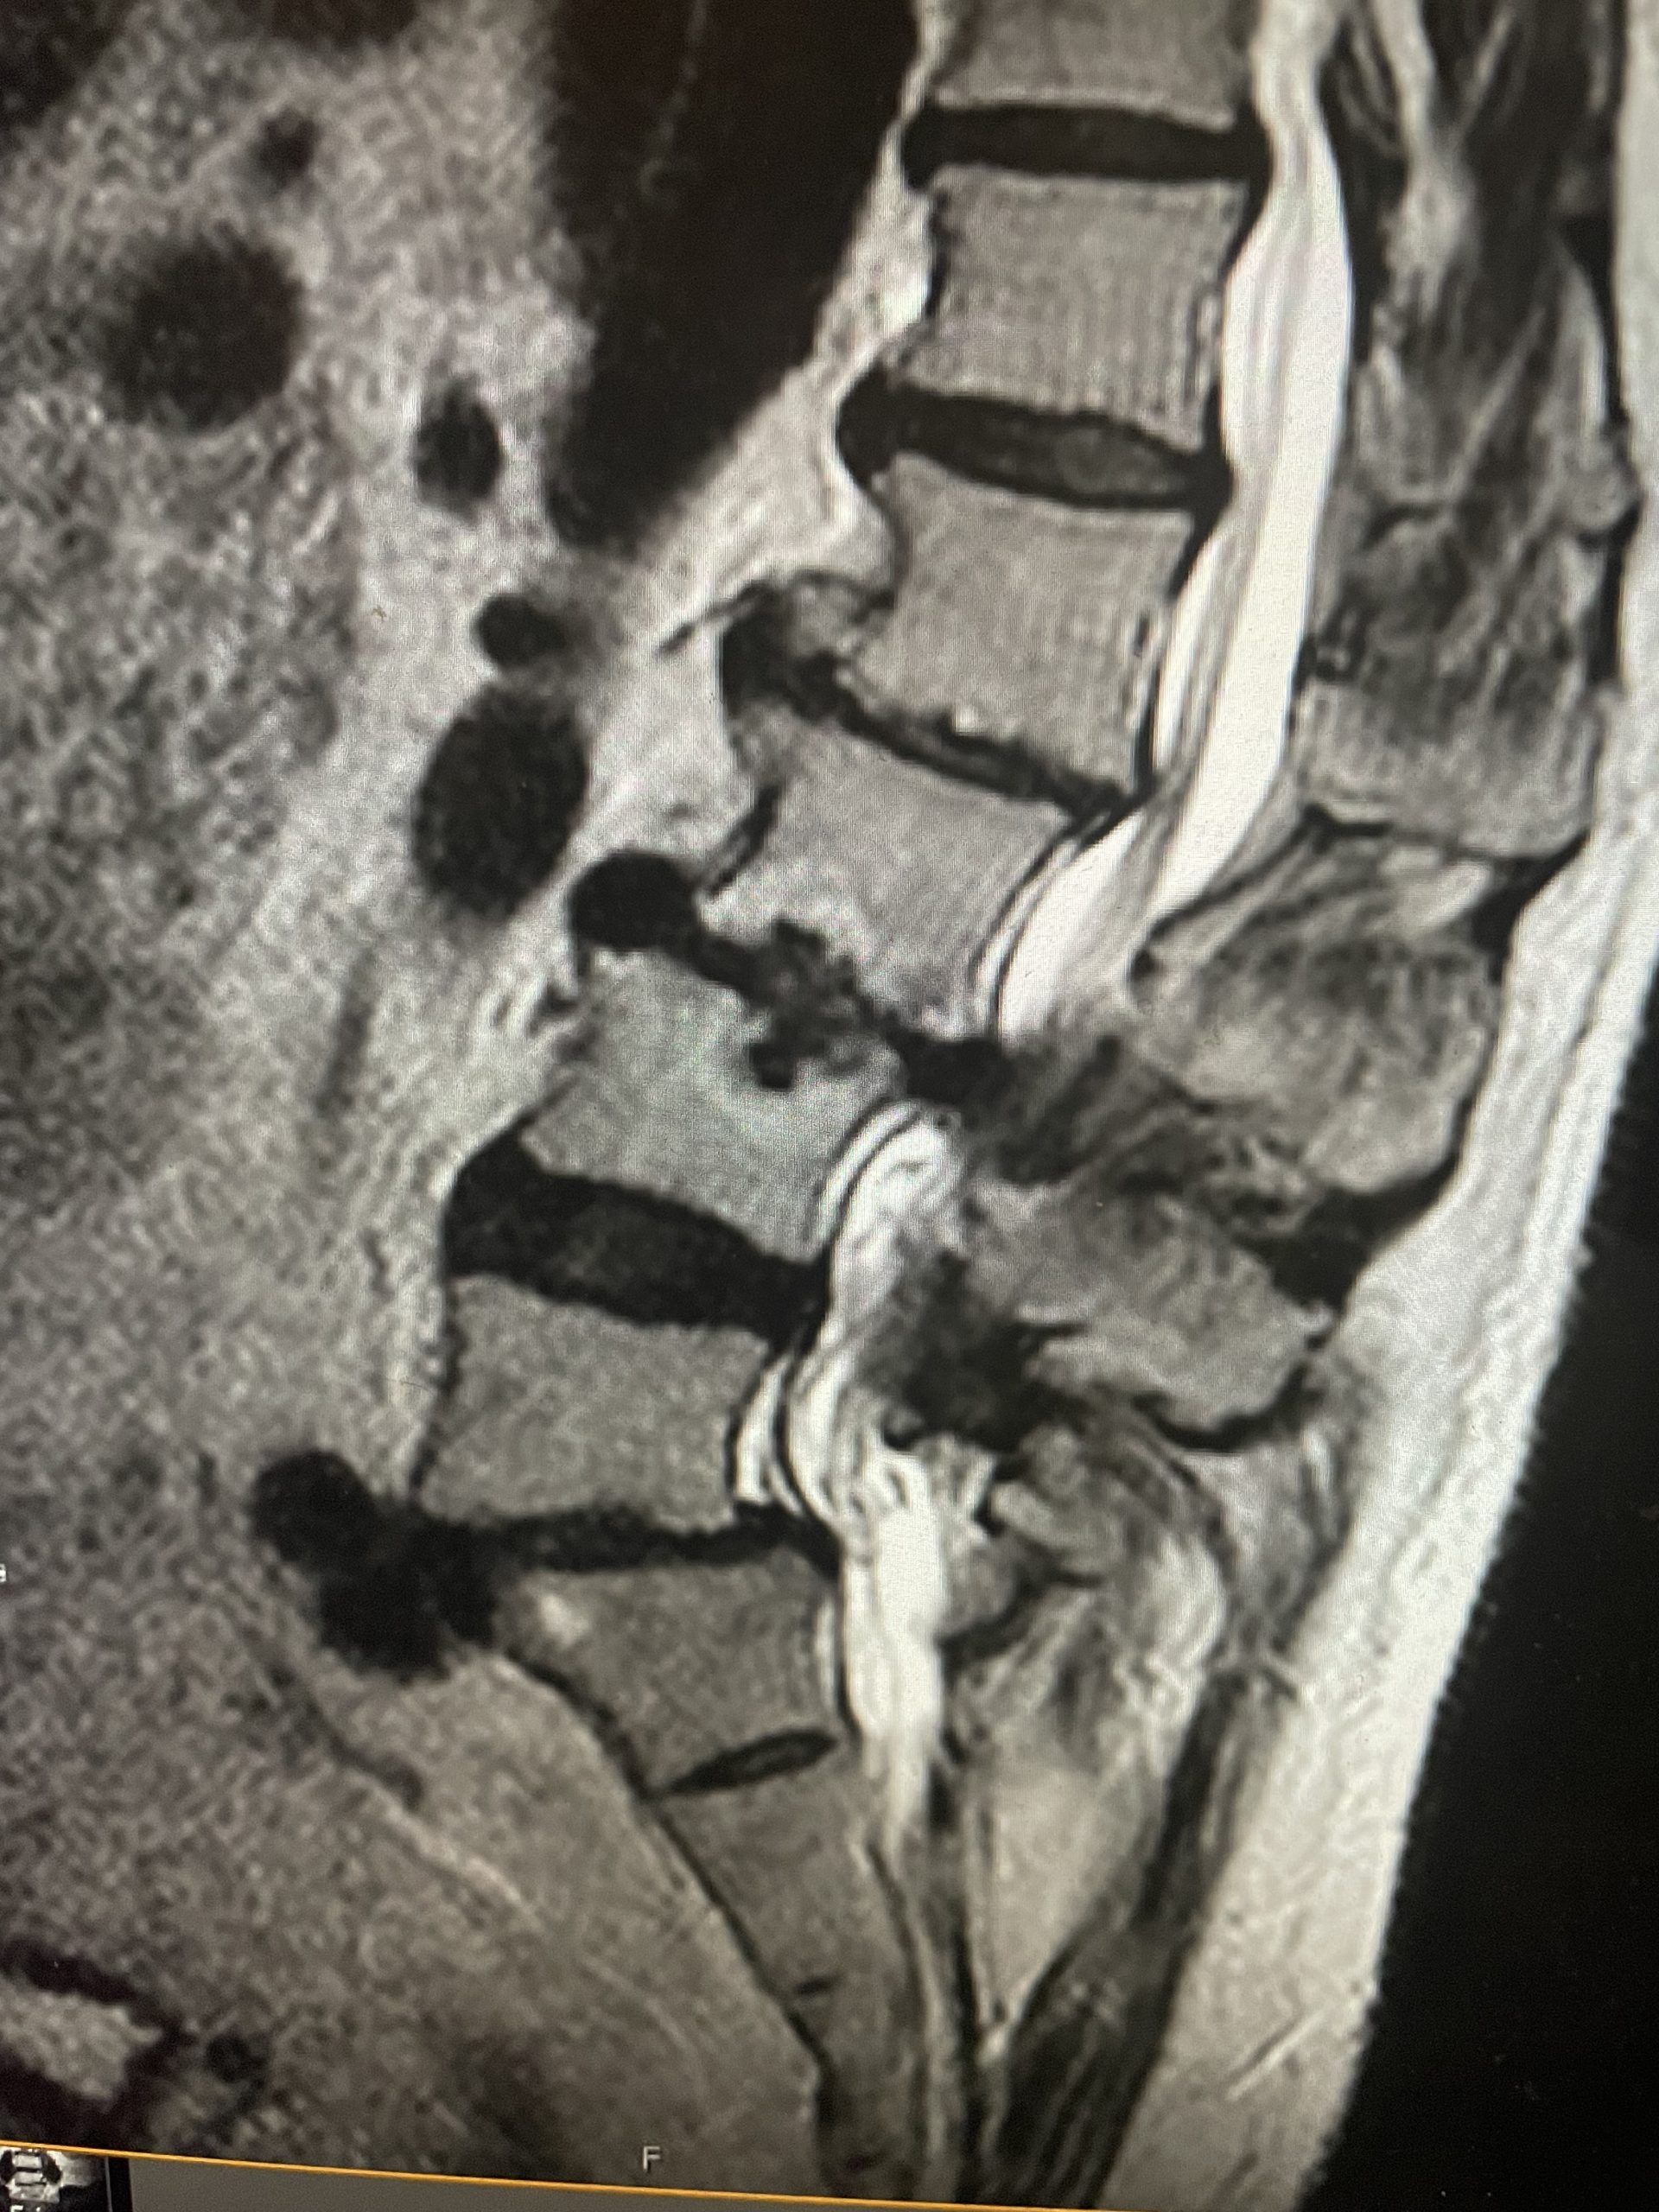

This 72 year old female had a long history of low back pain, leg pain, and scoliosis for which ten years ago she had a lumbar laminectomy followed by an instrumented L4-S1 fusion a year later. Since that time she had progressive low back pain and right lower extremity, weakness, and numbness. She presented with her leg symptoms being the biggest problem. MRI demonstrated a degenerative scoliosis with severe stenosis above the L4-S1 laminectomy and instrumented fusion. She had severe L2-3 and L3-4 stenosis. (Figs.3a,3b,3c 3d). After failing conservative management, she underwent an L2-L4 revision laminectomy and in situ fusion. She did well postoperatively. Considerations in performing a revision spine surgery is scar formation which initially makes it challenging to identify landmarks even in the region above that was not previously operated on. And of course during the dissection of compressive material on the dura, it is difficult to identify planes of separation and therefore an increased risk of a CSF leak. It was felt because of the severity of the scoliosis and her age we augmented the laminectomy with an in situ fusion, or a fusion with just bone graft without instrumentation. It is controversial whether a fusion is actually necessary in the case of a stable degenerative scoliosis with stenosis but the accepted approach is to perform a fusion If an instrumented fusion is considered it would require at least a T11-pelvis fusion. Since we performed only a 2 level laminectomy with a severely osteophytic spine, we compromised with an in situ fusion, reducing blood loss, operating time, and risk for infection. Because of the degree of spondylotic disease as a result of the stresses and strains on the spine given the scoliosis, the spine attempts to auto stabilize by forming these buttresses of arthritic material.

Fig 3a: Coronal T2-weighted MRI demonstrating significant detro lumbar degenerative scoliosis with a prior L4-S1 instrumented fusion. Note lateral listhesis of the L3-4; Figs 3b and 3c: Sagittal and axial T2- weighted MRIs showing severe lumbar stenosis above the prior L4-S1 fusion; Fig 3d showing an axial image T2-weighted MRI at the level of the prior L4-5 portion of the fusion showing no recurrent stenosis